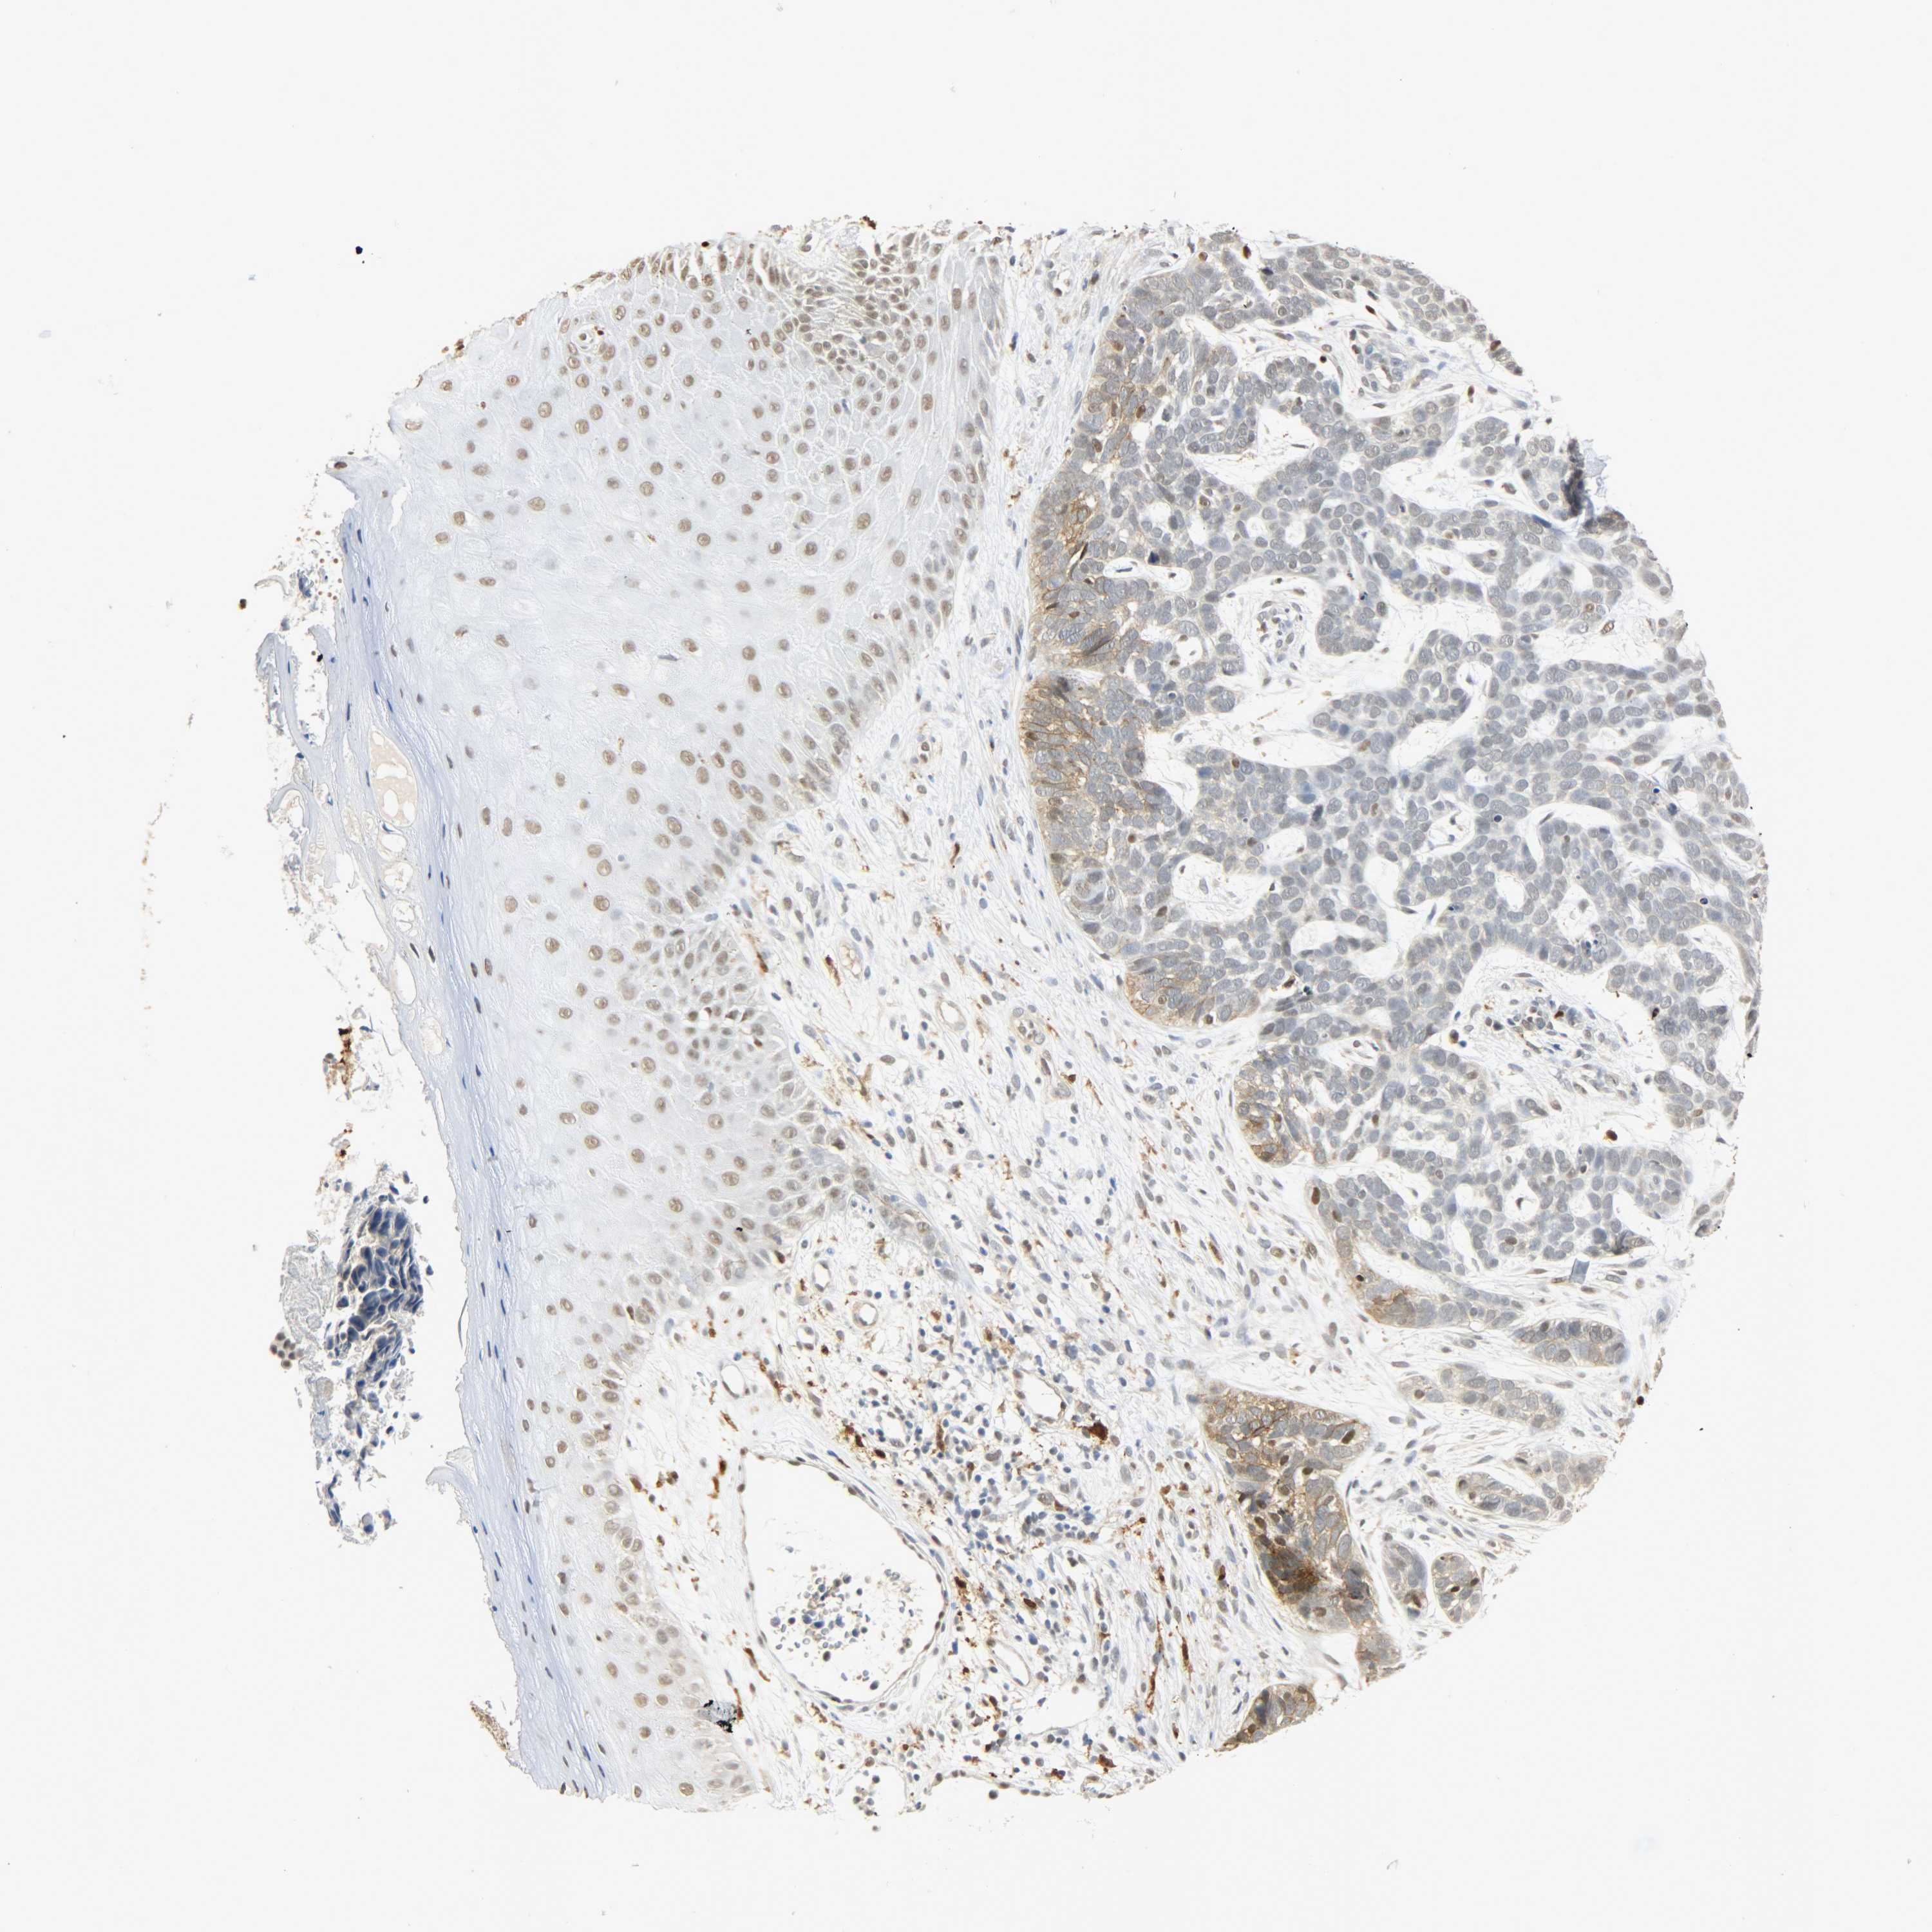

SKIN CANCER - Protein expressioni

A mouse-over function shows sample information and annotation data. Click on an image to view it in a full screen mode. Samples can be filtered based on level of antibody staining by selecting one or several of the following categories: high, medium, low and not detected. The assay and annotation is described here.

Antibody staining in the annotated cell types in the current human tissue is reported as not detected, low, medium, or high, based on conventional immunohistochemistry profiling in selected tissues. This score is based on the combination of the staining intensity and fraction of stained cells.

Each image is clickable and will lead to virtual microscopy that enables deeper exploration of all samples and also displays staining intensity scores, fraction scores and subcellular localization as well as patient and tissue information for each sample.

Antibody HPA004765

Antibody CAB000143

Antibody CAB001995

Squamous cell carcinoma, NOS

Basal cell carcinoma